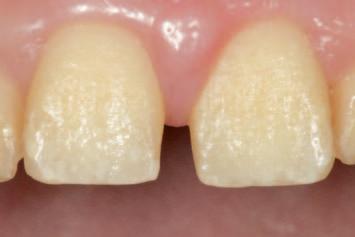

n Before initiating tooth preparation with diamond burs under copious water coolant, highly visible contrasting marks should be applied to the window perimeter of the preparation guide adjacent to the identified areas of

interference (Figure 3). These visual cues enhance intra-operative visibility and reduce the risk of over-preparation, which can occur when the guide’s reference contours are obscured by the coolant spray.

FIGURE 3: Pre-operative marking of the preparation guide with a visually contrasting colour prior to tooth reduction.

A C B